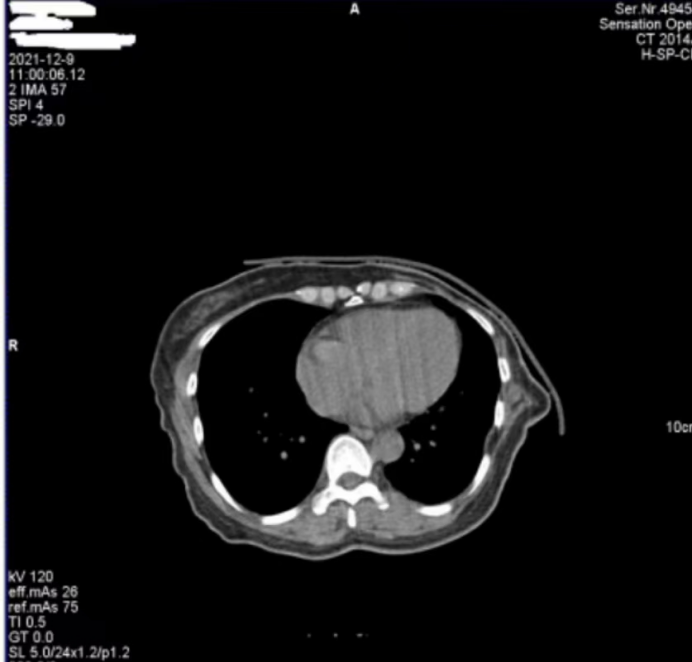

醫(yī)院反映,西門子Definition型CT機在進行患者掃描時,圖像上會偶發(fā)兩種偽影。一種是斜線狀偽影(圖 1),另一種是中心不規(guī)則高密度偽影(圖 2)。其中,斜線狀偽影對診斷影響較大,時常導致醫(yī)生無法準確判斷患者病灶情況,醫(yī)院希望我們盡快排查并解決問題。

圖1

對于圖 1 中的斜線狀偽影,我們第一時間查看了設備的錯誤日志和球管歷史記錄,然而并未發(fā)現(xiàn)球管存在打火情況的相關信息。但仔細觀察圖 1 中的 S35C0,結合我們多年的維修經(jīng)驗,這一參數(shù)特征明確指向在當時的掃描曝光時刻,球管存在打火現(xiàn)象。球管打火會直接干擾射線的穩(wěn)定輸出,進而在圖像上形成這種斜線狀偽影,這也解釋了為何該偽影會對診斷造成較大影響。